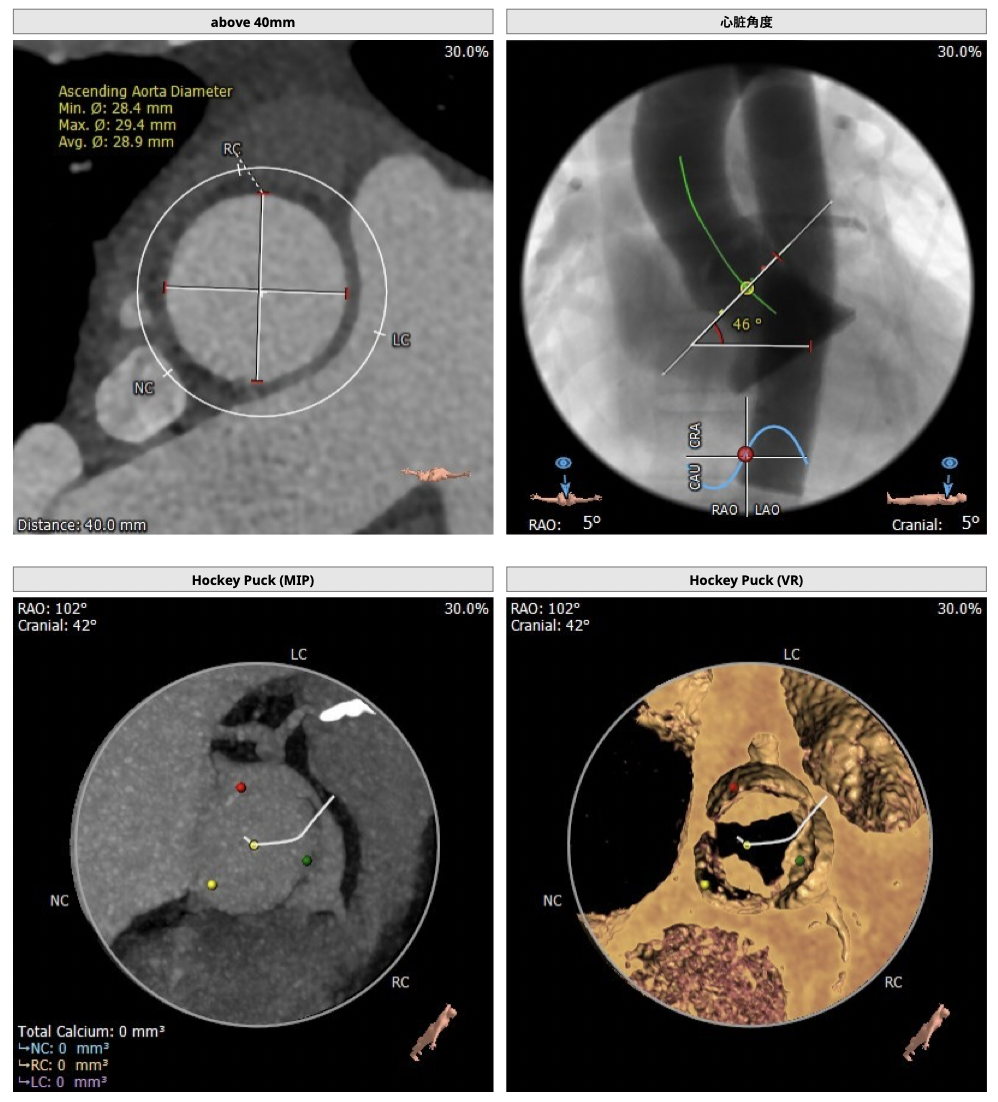

超声提示:主动脉瓣重度狭窄伴中度关闭不全,主动脉瓣口面积:0.8cm2主动脉向前速度:418cm/s,左房增大(40mm),左室肥厚伴舒张功能减退,少量心包积液,EF:64%。

②主动脉根部钙化较轻,瓣叶肥厚,各交界缘不同程度粘连,瓣膜释放后具有瓣周漏风险;

③左冠高度不高,且瓣叶冗长,达冠脉开口层面,且冠脉存在狭窄,存在冠脉阻塞的风险;

确保冠脉安全,拟采取PCI+TAVR一站式手术策略,因患者右侧股动脉钙化严重、入路狭窄,拟采取无鞘法从右股动脉穿刺入路,选用20mm球囊预扩、L23号VenusA-Valve瓣膜、采用VenusA-Plus输送系统确保瓣膜的精确释放,瓣膜释放后结合造影和超声情况,决定是否后扩。